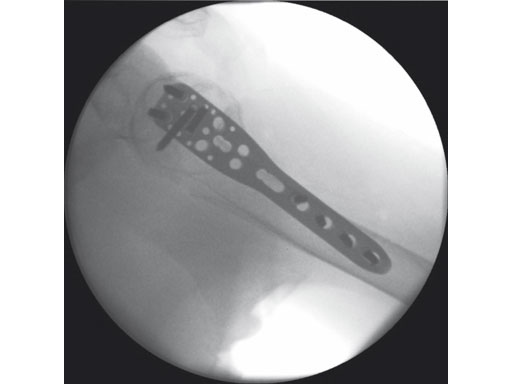

The 3.5 mm LCP percutaneous aiming system for PHILOS offers the possibility to insert the PHILOS plate through the transdeltoid approach and to insert the shaft screws percutaneously enabling a less-invasive application of PHILOS.

Overall, the 3.5 mm LCP percutaneous aiming system facilitates plate insertion as well as positioning and adjustment.